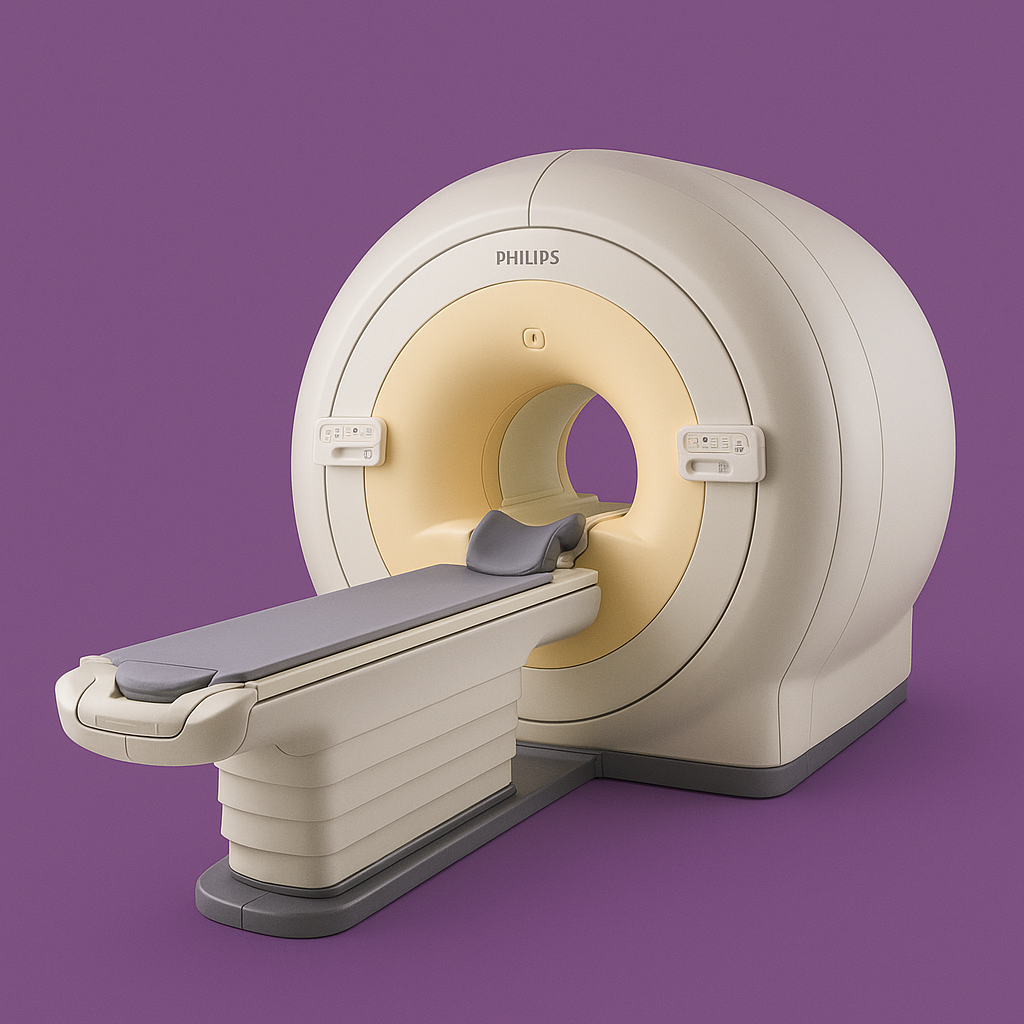

Магнітно-резонансний томографи Philips Achieva 1.5T, Intera1.5T

Високопольний МРТ-сканер, що забезпечує виняткову якість зображення, швидке сканування та комфорт пацієнта. Ідеальний для точних діагностичних досліджень у всіх клінічних напрямках.

• Потужне магнітне поле 1.5 Тл — висока чіткість та деталізація

• Швидкі протоколи та зменшення артефактів руху

• Розширені послідовності для дослідження мозку, хребта, суглобів і органів

• Комфортна широка тунельна система та тихе сканування

• Оптимальний вибір для рутинних і складних МРТ-досліджень